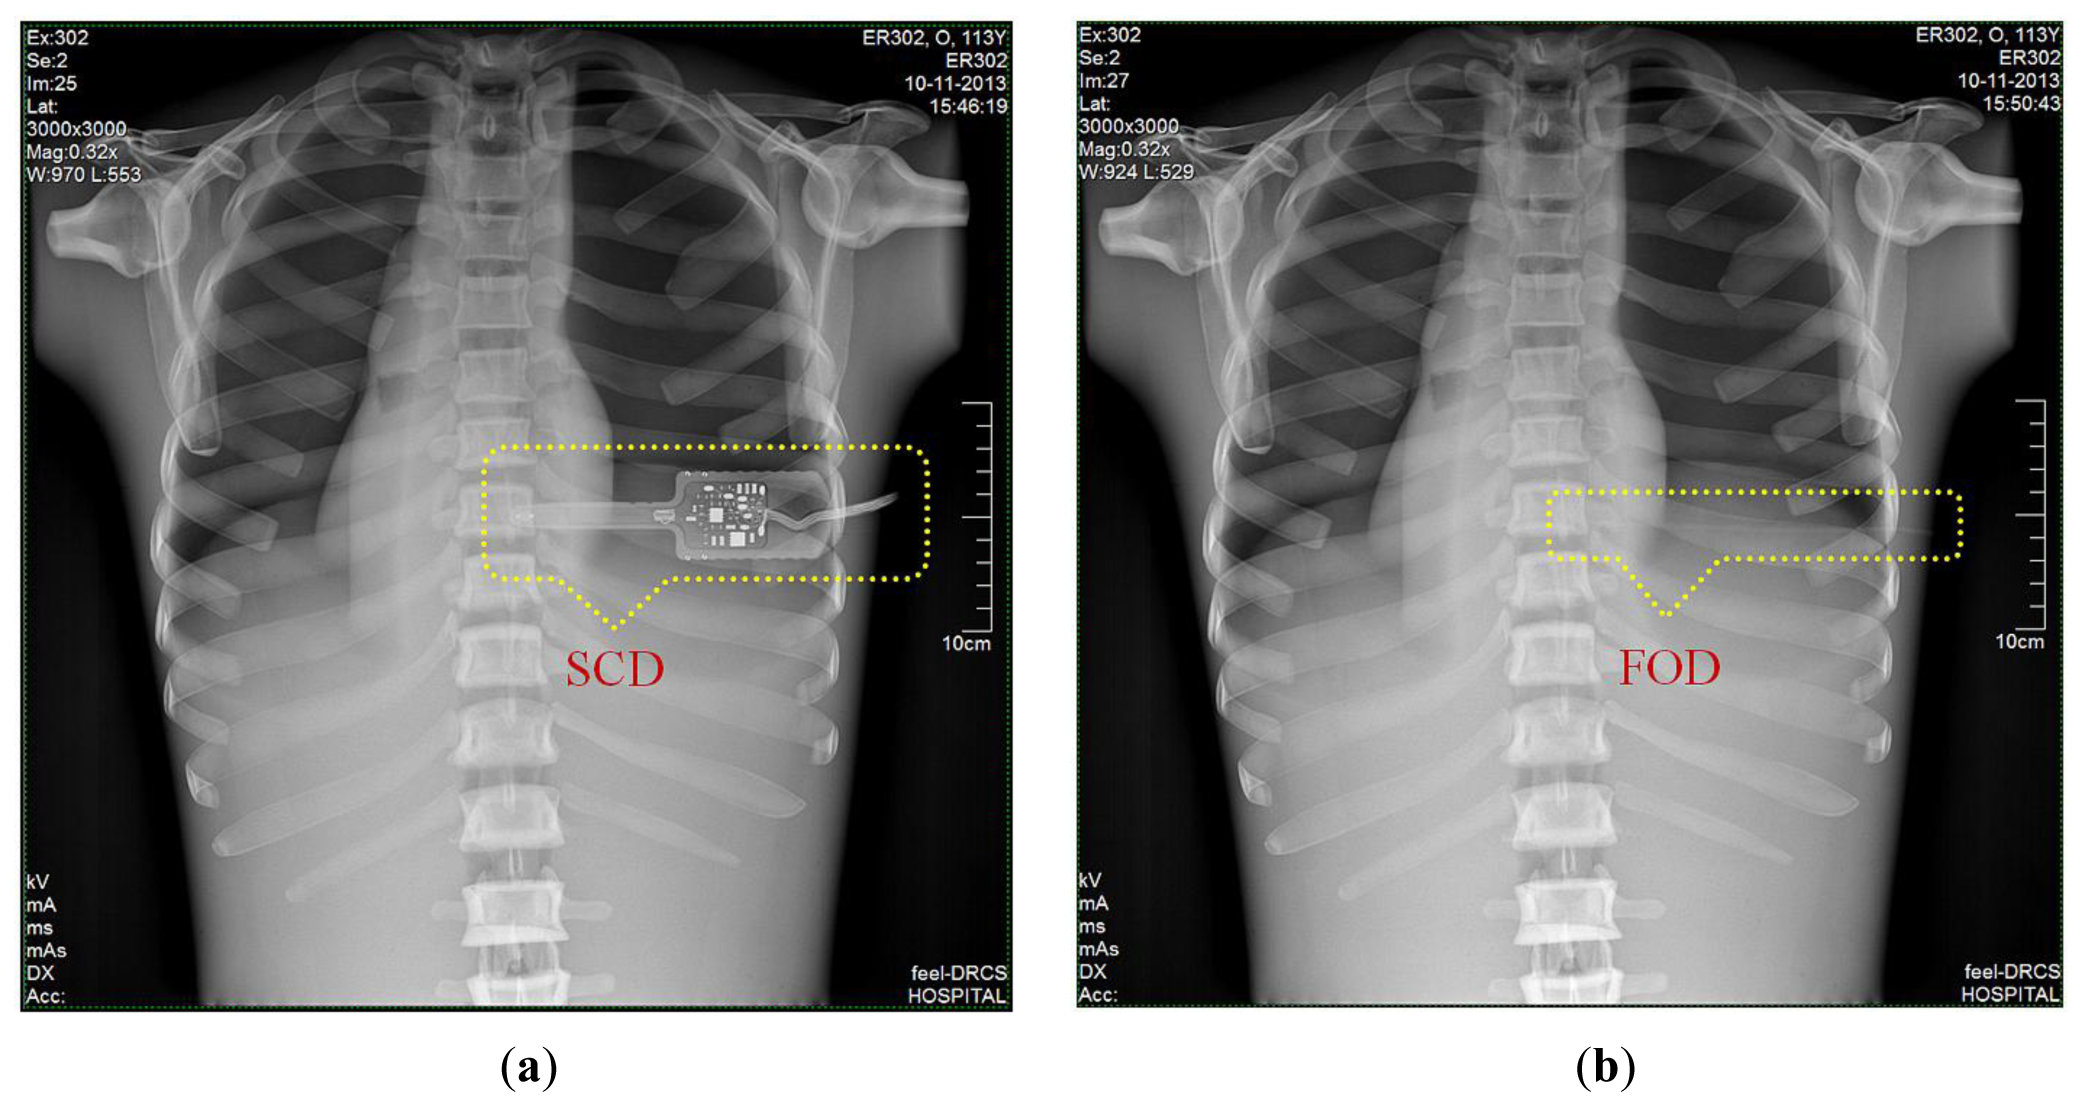

3.6. DR Images of Anthropomorphic Thorax Phantom

Finally, we obtained DR images from a posteroanterior (PA) chest examination using a flat panel detector of the DR system. In this evaluation, the values of the tube potential, current-time product (tube current x irradiation time), FID, and field size were set at 110 kVp, 10 mAs (320 mA × 32 ms), 180 cm, and 30 × 30 cm2, respectively. Figure 9a,b shows two DR images of the anthropomorphic thorax phantom with the finger-shaped dose sensor of the SCD and the sensing probe of the FOD, respectively. To measure real-time ESD and to evaluate the effects of the dosimeter on the image artifacts during PA chest radiography, each distal end of two different dosimeters was placed sequentially at the center of the beam field on the thorax phantom. As can be seen in Figure 9a, the SCD caused image artifacts due to its large size and high-atomic-number materials and, accordingly, the image interfered with the examination of radiation imaging. On the other hand, the FOD makes it possible to measure the ESD with minimization of image artifacts, as shown in Figure 9b, because its size is very small compared to the SCD and it consists of low-atomic materials (i.e., near tissue-equivalent materials) [5]. Particularly, we can expect that the constituent materials of the sensing probe will attenuate X-ray photons in a similar way as the density and atomic compositions of the PSF, POF, and black jacket are quite well matched [22,23].

In this study, we fabricated a miniature FOD system using a PSF, a POF, and an MPPC module for measuring real-time ESD with minimization of artifacts in the DR image during medical imaging tasks. While varying the exposure parameters of a DR system, we measured the scintillating light related to the ESD using the sensing probe of the FOD, which was placed at the center of the beam field on the anthropomorphic thorax phantom. From the experimental results, the total counts of the proposed FOD system were changed in a manner similar to the ESDs including backscatter simultaneously obtained using a conventional SCD. In particular, we demonstrated that the total counts of the FOD are only affected by the ESD values even though each exposure parameter is changed independently. As functions of each exposure parameter, such as tube potential, tube current, irradiation time, and FSD, the relationships between the total counts of FOD and the ESDs and the best fit lines are presented in Figures 4, 5, 6, and 8 and their R2 values are very close to 1. In the range of ESD values less than 1 mGy, the mathematical relation between the total counts of FOD (x) and the ESDs (y) is y = 68939x2 + 84559x + 16099, regardless of the exposure parameters. However, this relation has a low accuracy because R2 is found to be 0.9794. Therefore, it is necessary to optimize hardware and software of the FOD system for measuring ESD with a high accuracy. Next, DR images were also obtained using a flat panel detector of the DR system to evaluate the effects of the dosimeter on image artifacts during PA chest radiography. The proposed FOD minimally affected the diagnostic information of radiation images while the SCD caused serious image artifacts due to its large size and high-atomic-number materials.